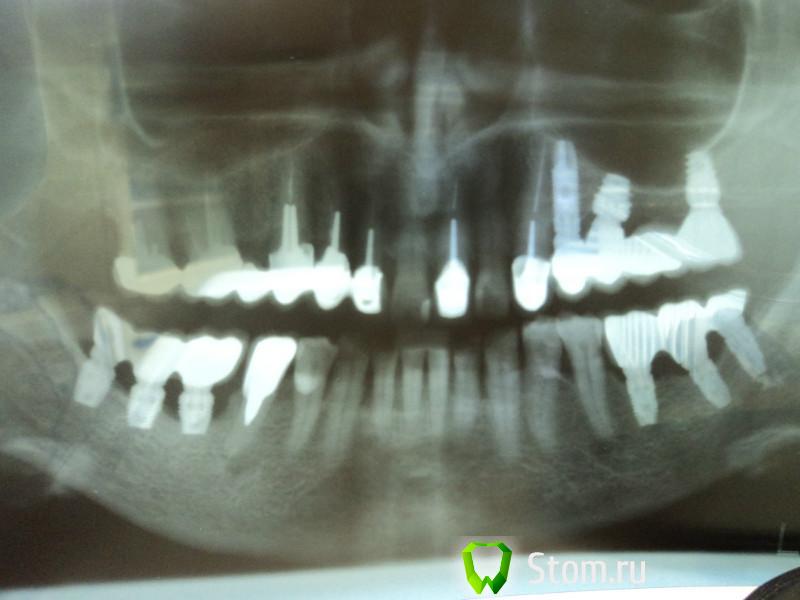

pit Опубликовано 1 мая, 2012 Поделиться Опубликовано 1 мая, 2012 (изменено) А я ушел с adin. Не нравится. Много рецессий через 6-12 месяцев после протезированияНедавно еще прозошел странный случайВообще-то странный случай произошел во время установки.Имплантаты установлены ПЛОХО!Планирование лечения ПЛОХОЕ! Изменено 1 мая, 2012 пользователем pit Ссылка на комментарий

laitzild Опубликовано 12 мая, 2012 Поделиться Опубликовано 12 мая, 2012 Вообще-то странный случай произошел во время установки.Имплантаты установлены ПЛОХО!Планирование лечения ПЛОХОЕ!В чем конкретно плохое планирование и плохая установка?а вы бы еще короче имплантаты взяли и так же криво поставили ))) Я понимаю, что у всех бывают неудачи, но не нужно их связывать с имплантатами.Имплантат в позиции 48 зуба не доходит до нерва 1.5-2.0 мм, хотя погрешность компьютерной томограммы имела место быть.В четвертом сегменте, о котором идет речь имплантаты установлены достаточно ровно.Я понимаю во втором сегменте с костью проблемы .Там короткие оправдано установлены.Возможно синуслифтингом доктор не владеет или пац ктегорически против... Ну в в третьем то что мешало учтановить мм по 15 ??В третьем сегменте имплантаты не доходят до нерва на 2-3 мм, на снимке плохо прослеживается верхняя граница нижнечелюстного канала. Ссылка на комментарий

Bier Опубликовано 12 мая, 2012 Поделиться Опубликовано 12 мая, 2012 в области 48 может и нормальной длины, но во первых зачем в области 48 вообще имплантат, во вторых почему нельзя было поставить в область 46 и 47 по длиннее и по тоньше ? и отработать с десной предварительно... Ссылка на комментарий

laitzild Опубликовано 12 мая, 2012 Поделиться Опубликовано 12 мая, 2012 В области 48 имплантат поставлен для предотвращения перегрузки протезной конструкции,как дополнительная опора, в позициях 46 и 47 зубов замеры по компьютерной томограмме показали расстояние 8-9 мм до нижнечелюстного канала. Т.к. кость очень широкая ,были выбраны имплантаты Swell ID 0650. На операции подборки имплантатов не было. А что Вы имеете в виду "отработать с десной"? С деснами проблем не было. Ссылка на комментарий

Bier Опубликовано 12 мая, 2012 Поделиться Опубликовано 12 мая, 2012 у вас там до канала, как до луны пешком... это раз. А что вы понимаете под "с деснами не было проблем"? )) Хорошо бы конечно еще фоточку из полости рта. Ссылка на комментарий